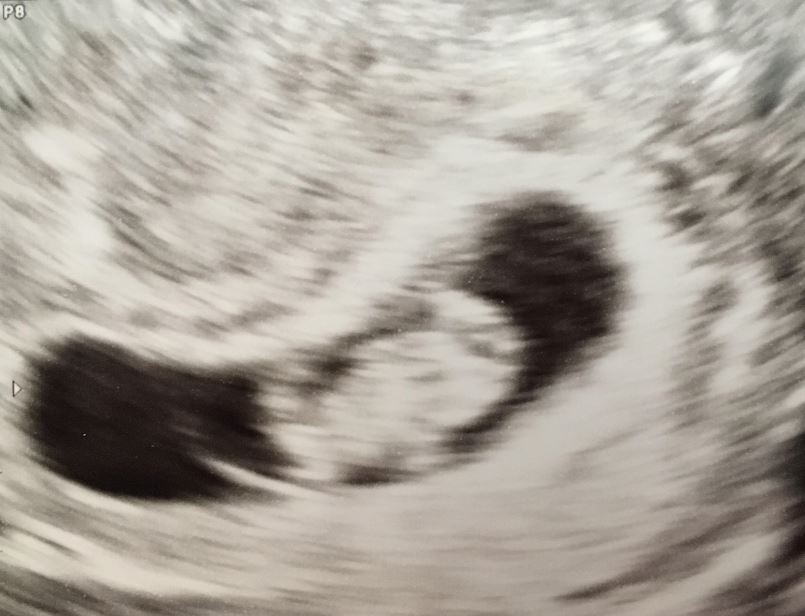

• I had my first ultrasound on Monday! I'm not as far along as I thought - I thought I was past 10 weeks but I'll be just 10 weeks tomorrow. So glad I decided to have an early ultrasound - last pregnancy I just had one at 20 weeks. This time around I was having cramping and bleeding and something seemed off. I guess this is why!!!! Seeing double!! They think identical but can't quite be certain yet as I only wanted an abdominal ultrasound this visit. Needless to say I'm freaking out! New due date of November 8th instead of the 3rd...but I'm sure with twins it may be October!

Holy cow, identical twins!! Congratulations! The hospitals I've worked at deliver identical twins no later than 36 weeks (which I believe is the recommendation) due to the increased risks if you go past that. FX for a smooth pregnancy for you!